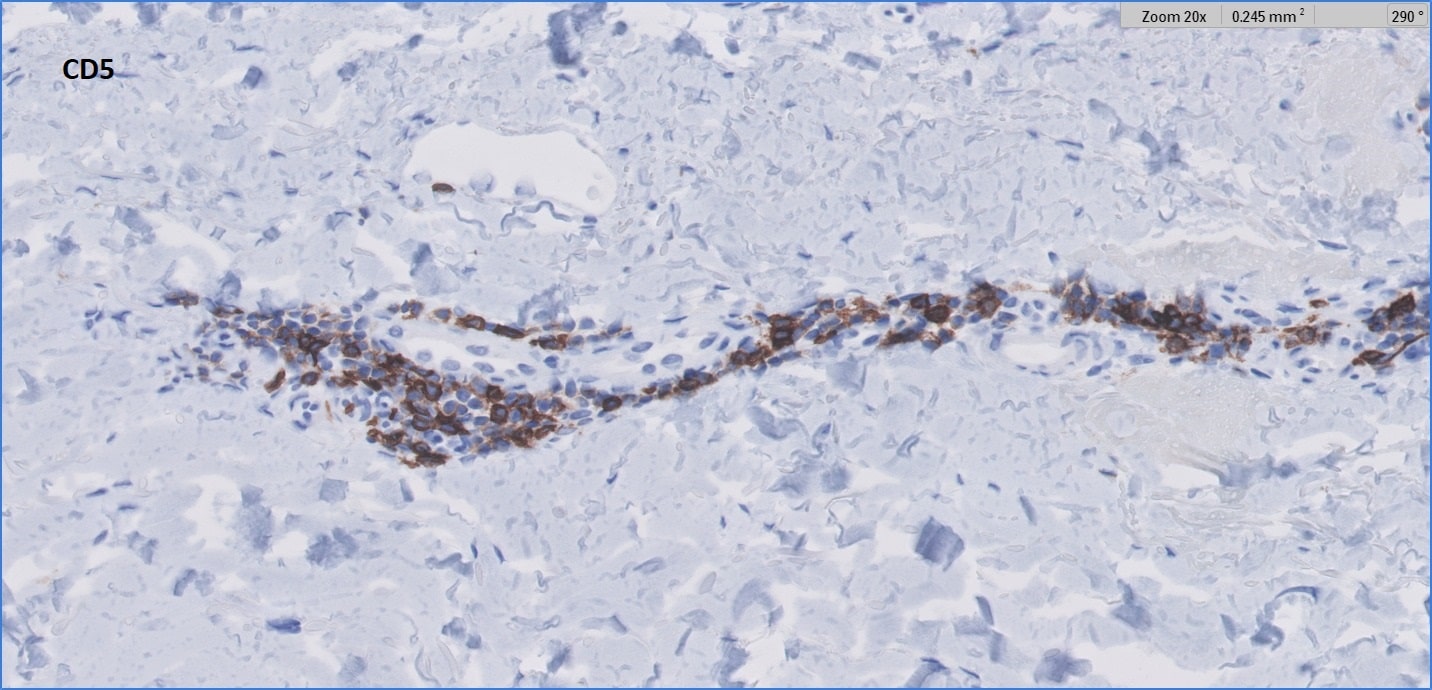

CD5-min